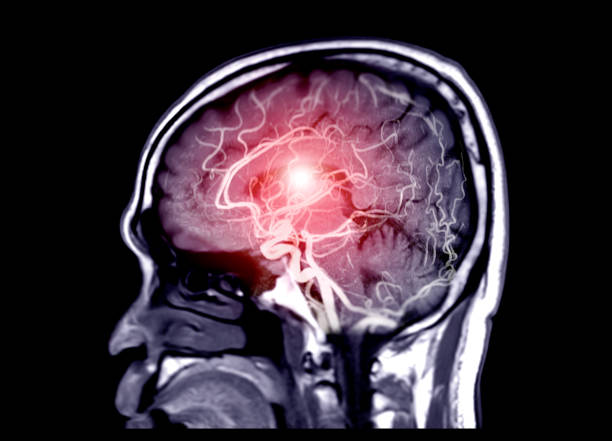

뇌출혈은 뇌안에 있는 혈관에서 출혈이 발생하여 뇌조직이 손상을 입는 질환이며, 중증의 뇌혈관질환 중 하나입니다. 일반적으로 고혈압, 동맥류, 혈관 기형, 혈전 등의 이유로 혈관이 파열하거나 뚫리면서 발생합니다.

고혈압은 뇌출혈을 일으키는 가장 일반적인 원인 중 하나입니다. 고혈압은 혈관벽을 약화시켜 혈관이 파열하기 쉽게 만들기 때문입니다. 또한, 혈관에 생긴 약간의 이상증상이나 동맥류, 혈관 기형 등도 뇌출혈의 원인이 될 수 있습니다.